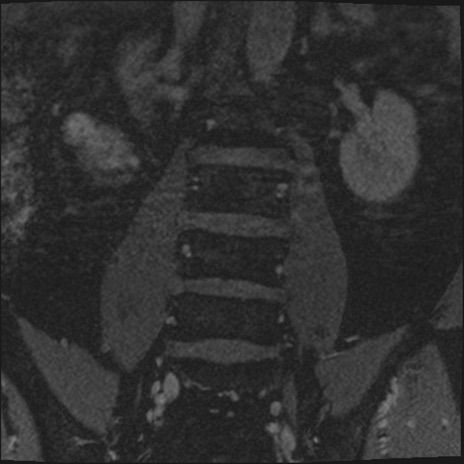

【整形】TIPS症例2 腰椎MRI 3D(冠状断像)

【症例】70歳代男性

【主訴】左下肢痛

【現病歴】2週間前くらいから腰痛、左下肢痛あり。左臀部から大腿、下腿外側のしびれが常時ある。歩行とともに同部位の痛みあり。

【身体所見】Lasegue70-/60+、Bragard-/±、PTR ±/±、ATR -/-、IP 5/5、TA 5/4、TS 5/5、EHL 右第1足趾なし/3、FHL 5/5、hypersthesia(-)、足背動脈触知良好

異常所見と診断は?